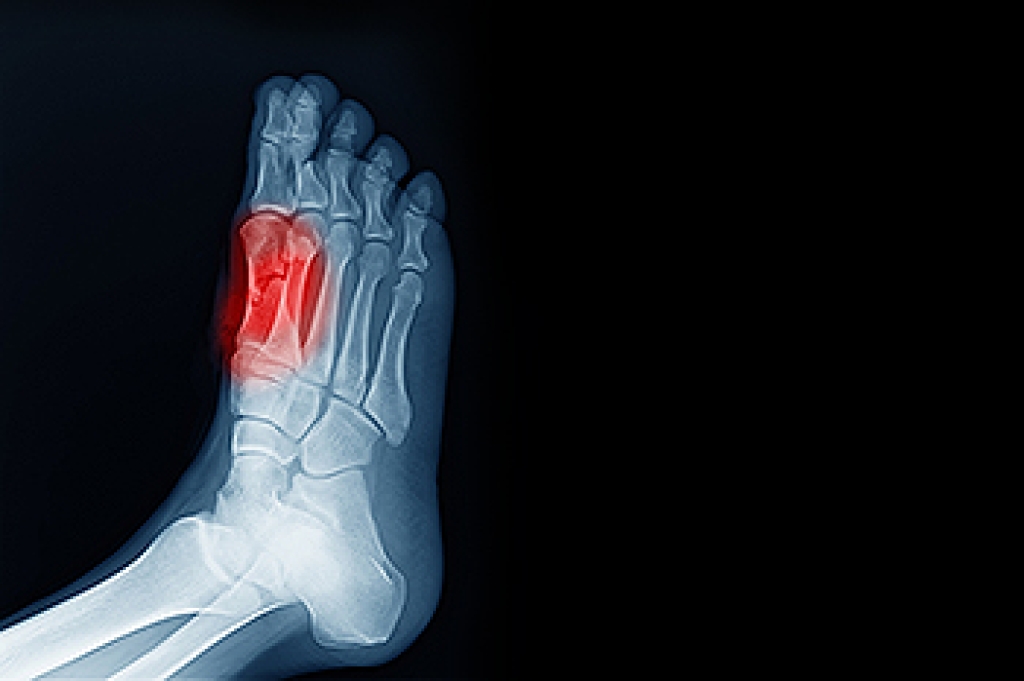

Sesamoiditis causes pain beneath the big toe and is often exacerbated by weight-bearing and specific footwear choices. The two tiny sesamoid bones, located just below the big toe, are integral to foot locomotion. They can be affected by direct trauma or positional changes, especially in individuals with high-arched feet, bunions, or those who wear high heels. For dancers, joggers, and those individuals with certain foot structures, the discomfort associated with sesamoiditis can be particularly challenging. Diagnosis by a podiatrist relies on examination of the toe, and determining range of motion. Other tests, such as synovial fluid analysis and X-rays, may be used to exclude infection and fractures. Pain from sesamoiditis is often intensified by walking and may involve inflammation, warmth, and swelling around the 1st metatarsophalangeal, or MTP, joint. Footwear modification and custom orthotics can play a pivotal role in managing symptoms. Wearing thick-soled shoes may also help alleviate sesamoid pressure. In cases where a sesamoid fracture without displacement is identified, treatment involves immobilizing the joint with a flat, rigid, surgical shoe. For help with pain resulting from sesamoiditis, it is suggested that you schedule an appointment with a podiatrist for an exam and treatment.

Sesamoiditis is a condition of the foot that affects the ball of the foot. It is more common in younger people than it is in older people. It can also occur with people who have begun a new exercise program, since their bodies are adjusting to the new physical regimen. Pain may also be caused by the inflammation of tendons surrounding the bones. It is important to seek treatment in its early stages because if you ignore the pain, this condition can lead to more serious problems such as severe irritation and bone fractures.